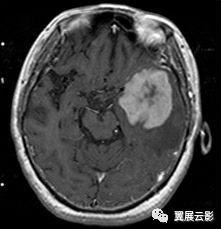

脑部囊肿是不是就是脑部肿瘤

总之,脑内囊肿尽管不是肿瘤,也尽管没有肿瘤那么严重,但若不采用神经外科手术或内腔镜治疗,其危害也是很严重的!如果你有了躯体症状就要尽快手术治疗。

囊肿又名囊性肿瘤,是良性肿瘤的一种。囊肿外面有一层包膜,包膜内包的是液体物质。肿瘤分成良性和恶性肿瘤。良性肿瘤只是体积增大,不引起转移,恶性肿瘤容易转移。